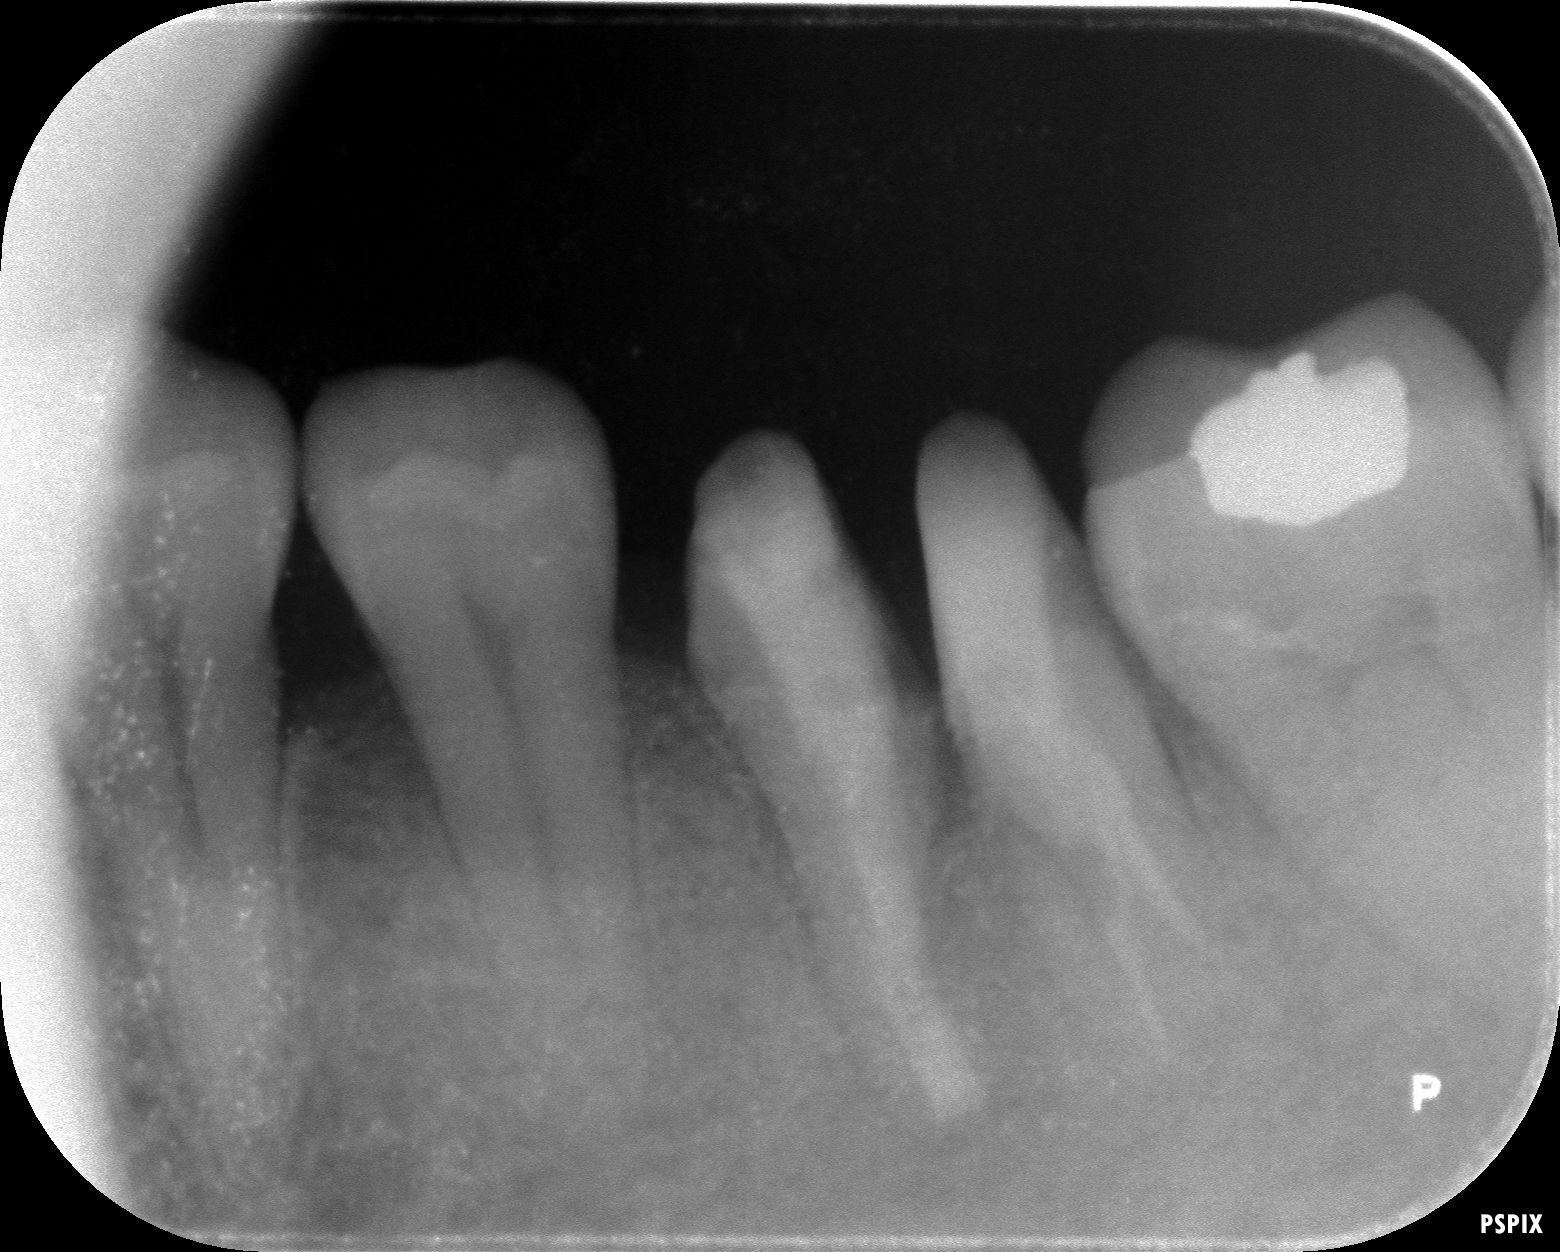

術前のレントゲン写真です。

根の先に膿の袋があります。(レントゲン透過像)

術後3ヶ月でのレントゲン写真です。

術後の経過は良好で、根尖部の透過像(膿の袋)は無くなりました。